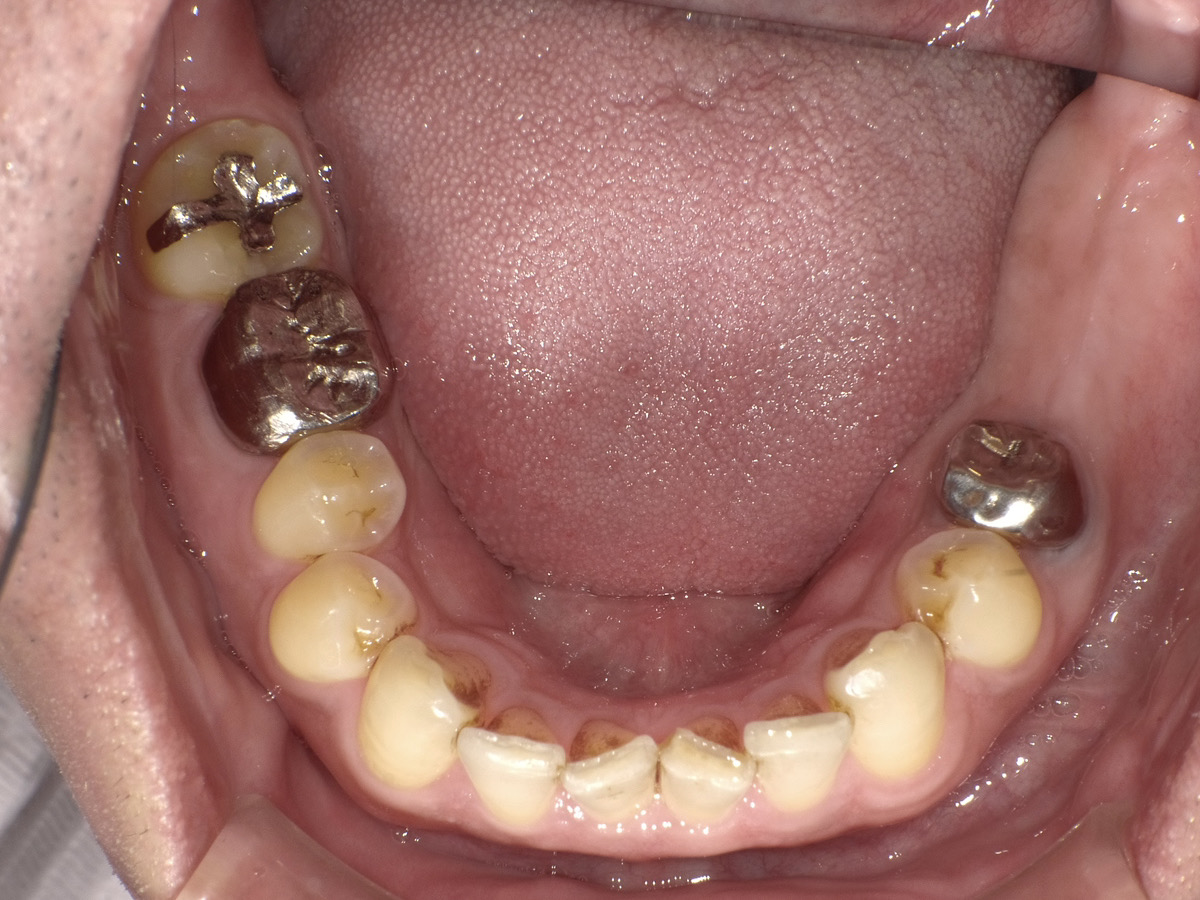

治療前

| 年齢・性別 | 40代・男性 |

| 主訴 | 左下7番の抜歯後、欠損部を補いたい。 ブリッジによる治療で健康な歯を削ることに抵抗があるため、左下6・7番にインプラントを希望。 |

| 治療内容 | 左下7番がむし歯により状態悪く抜歯後、ギシだと両側の歯を削っての作製で、健康な歯を削る事が気になるので元々欠損していた左下6番と一緒に2本分インプラントで進めていきたい。 |